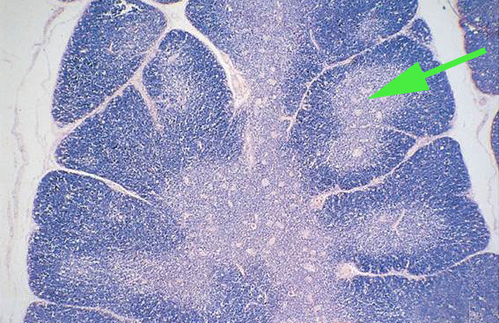

germinal center of a lymphatic nodule.

This is low power image of what organ? thymus

The light area surrounded by a thin dark area is called a

lymphatic nodule.